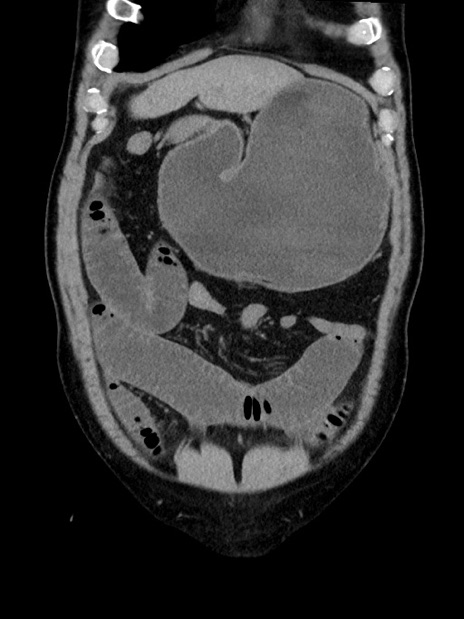

症例35(冠状断像)

【症例】70歳代 男性

【主訴】腹部膨満、嘔吐

【現病歴】昨日より腹部膨満感出現。本日増悪し、仙痛出現。嘔吐あり、受診。

【既往歴】糖尿病、胆摘後

【身体所見】BP 149/80mmHg、HR 74/min、BT 35.9℃、腹部:膨満、軟、圧痛なし。腸雑音減弱あり。上腹部正中切開瘢痕あり。

【データ】WBC 13500、CRP 1.72

横断像